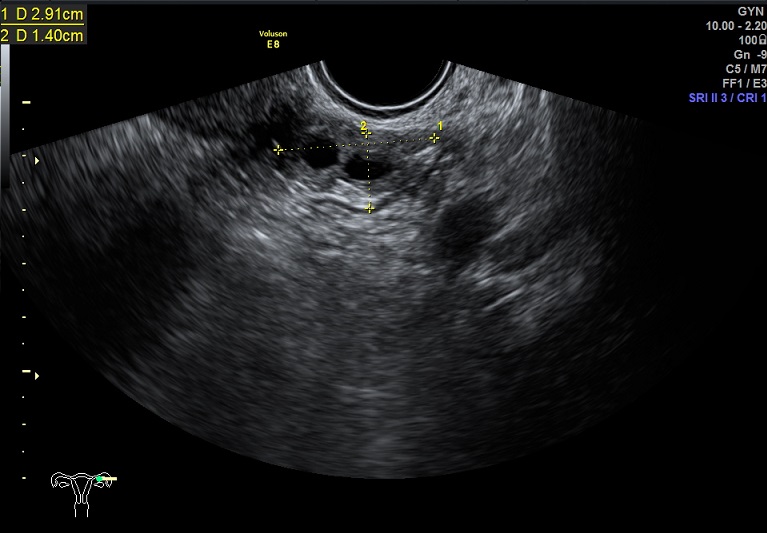

2015-1-12,月经第3天检查

左卵巢: 大小2.9x2.3x1.4cm 体积:4.8 窦卵泡:4个 卵巢间质血流:9.8cm/s RI:0.49